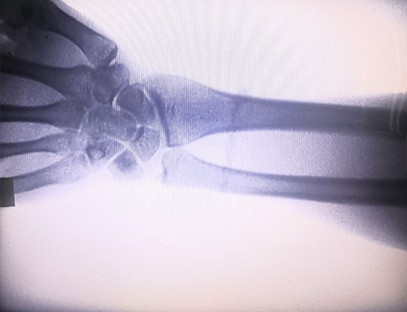

Is táirge ardchaighdeáin é ár Meaisín X-gha Ortaipéideach a dearadh go háirithe le haghaidh íomháithe ortaipéideacha. Is féidir é a úsáid le haghaidh diagnóis agus pleanáil cóireála ar choinníollacha ortaipéideacha éagsúla, lena n-áirítear bristeacha, dislocations, airtríteas, agus siadaí cnámh. Tá sé feistithe le teicneolaíocht X-gha chun cinn a chuireann ar chumas íomhánna ardcháilíochta le nochtadh radaíochta laghdaithe. Tá córas íomháithe ardtaifigh ag an meaisín agus is féidir íomhánna d'aon struchtúr cnámh a ghabháil le soiléireacht mhór.

Is féidir ár Meaisín X-gha Ortaipéideach a úsáid i speisialtachtaí leighis éagsúla, lena n-áirítear ortaipéidic, néareolaíocht agus leigheas éigeandála. Is minic a úsáidtear é chun breathnú fluarascópach ar chnámha géaga daonna, ospidéil Tréidliachta agus peataí, Cóireáil créachtaithe ag láithreáin spóirt, foirgnimh, longa farraige, limistéir iargúlta agus láithreáin pháirce míleata. I measc cuid de na hiarratais chliniciúla tá:

1. Diagnóis bristeacha, dislocations, agus gortuithe cnámh eile.

2. Meastóireacht ar ghalair chomhpháirteacha mar airtríteas, galar degenerative comhpháirteach, agus oistéapóróis.